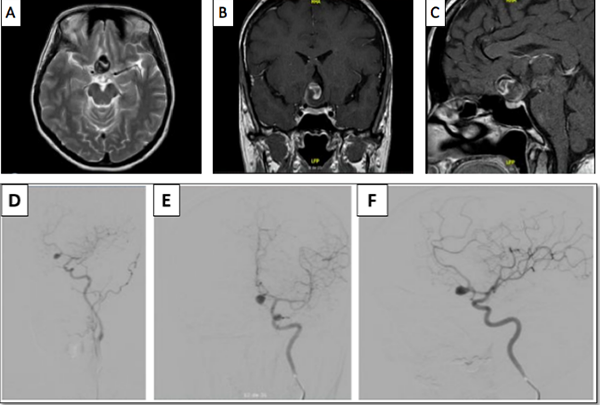

Luego del análisis del caso, y teniendo en cuenta la presencia del trombo intracavitario, el cuello del aneurisma, la posición favorable del saco aneurismático, y la edad de la paciente, se decidió que la cirugía era la mejor opción terapéutica, se realizó una craneotomía pterional derecha, y un abordaje transilviano bajo visión microscópica. Se encontró un aneurisma de gran tamaño dependiente de la AcomA (Figura 2), con dirección anteroinferior, calcificación en las paredes del domo y signos de trombosis. Una vez se identificó el cuello, y ambas A1 y A2, se posicionó un clip recto de 9 mm, que luego se reacomodó con otro clip definitivo de 9 mm, se retiró el previamente colocado, quedando con un solo clip definitivo. A continuación se comprobó la permeabilidad de los vasos A1 y A2, así como de la arteria recurrente de Heubner ipsilateral con doppler intraoperatorio. Se procedió con la disección del domo del aneurisma y trombectomía con aspirador ultrasónico, dejando el interior del aneurisma friable, y descomprimiendo de esta manera el nervio y el quiasma óptico. El procedimiento finalizó sin complicaciones, la paciente mejoró del déficit en el postoperatorio inmediato, y se llevó a arteriografía de control al día siguiente de la intervención, con la que se confirmó el adecuado clipaje de la lesión (Figura 3).

Figura 2 Secuencia quirúrgica. Se exponen los pasos más importantes. Disección de estructuras alrededor del aneurisma, el punto blanco señala el cuello del aneurisma expuesto y en azúl el domo (A). Clipaje del cuello (B). Aneurismectomía y trombectomía. La marca de color azúl indica el lóbulo temporal izquierdo, en blanco se observa el lóbulo frontal, y debajo de este se encuentra el aneurisma de ACoA abierto, por encima del domo marcado en color negro se puede observar el nervio óptico, y adyacente a este, en color rojo, se observa la arteria carótida interna, detrás del domo del aneurisma y en color amarillo, la arteria cerebral anterior izquierda cursa paralela al cuello del aneurisma (C)